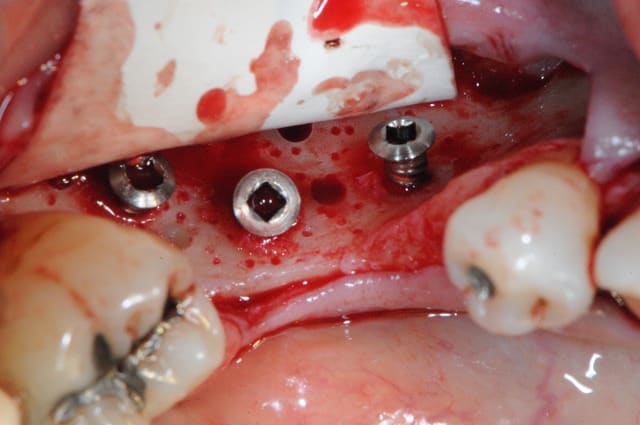

je devais mettre un implant de 6mm là où il n'y avait que 3.5 à4mm d'os. le reste des spires devaient être laissées en supra crestal et une ROG verticale devait être réalisée avec des vis Fast et une mesh titane + recouvrement par une membrane de péricarde.

au final j'ai replacé ma carotte et effectué ma ROG mais sans mettre mon implant.

en plus c'était la loose complète, j'ai du retirer mes mesh titanes car le lambeau s'est déchiré juste en face de la vis qui les maintenait.

ensuite la carotte devait être broyée et utilisé avec du maxgraft ou biobank en recouvrement des spires de l'implant. le tout devant être recouvert avec le mesh titane et des vis pour faire piquet de tente.

le problème, c'est qu'une partie de la gencive s'est déchirée et que par conséquent, je ne pouvait pas avoir l'assurance de refermer hermétiquement le site d'intervention. j'ai préféré replacer la carotte (en travers) pour gagner 1mm en hauteur et recouvrir avec un peu d'os et une membrane.